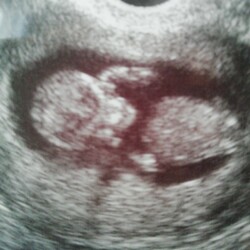

Ja hoor ik had ze eerst ook heel licht en elke 2 dagen zag je dat ze donkerder werden 馃槉 nu 8 weken zwanger